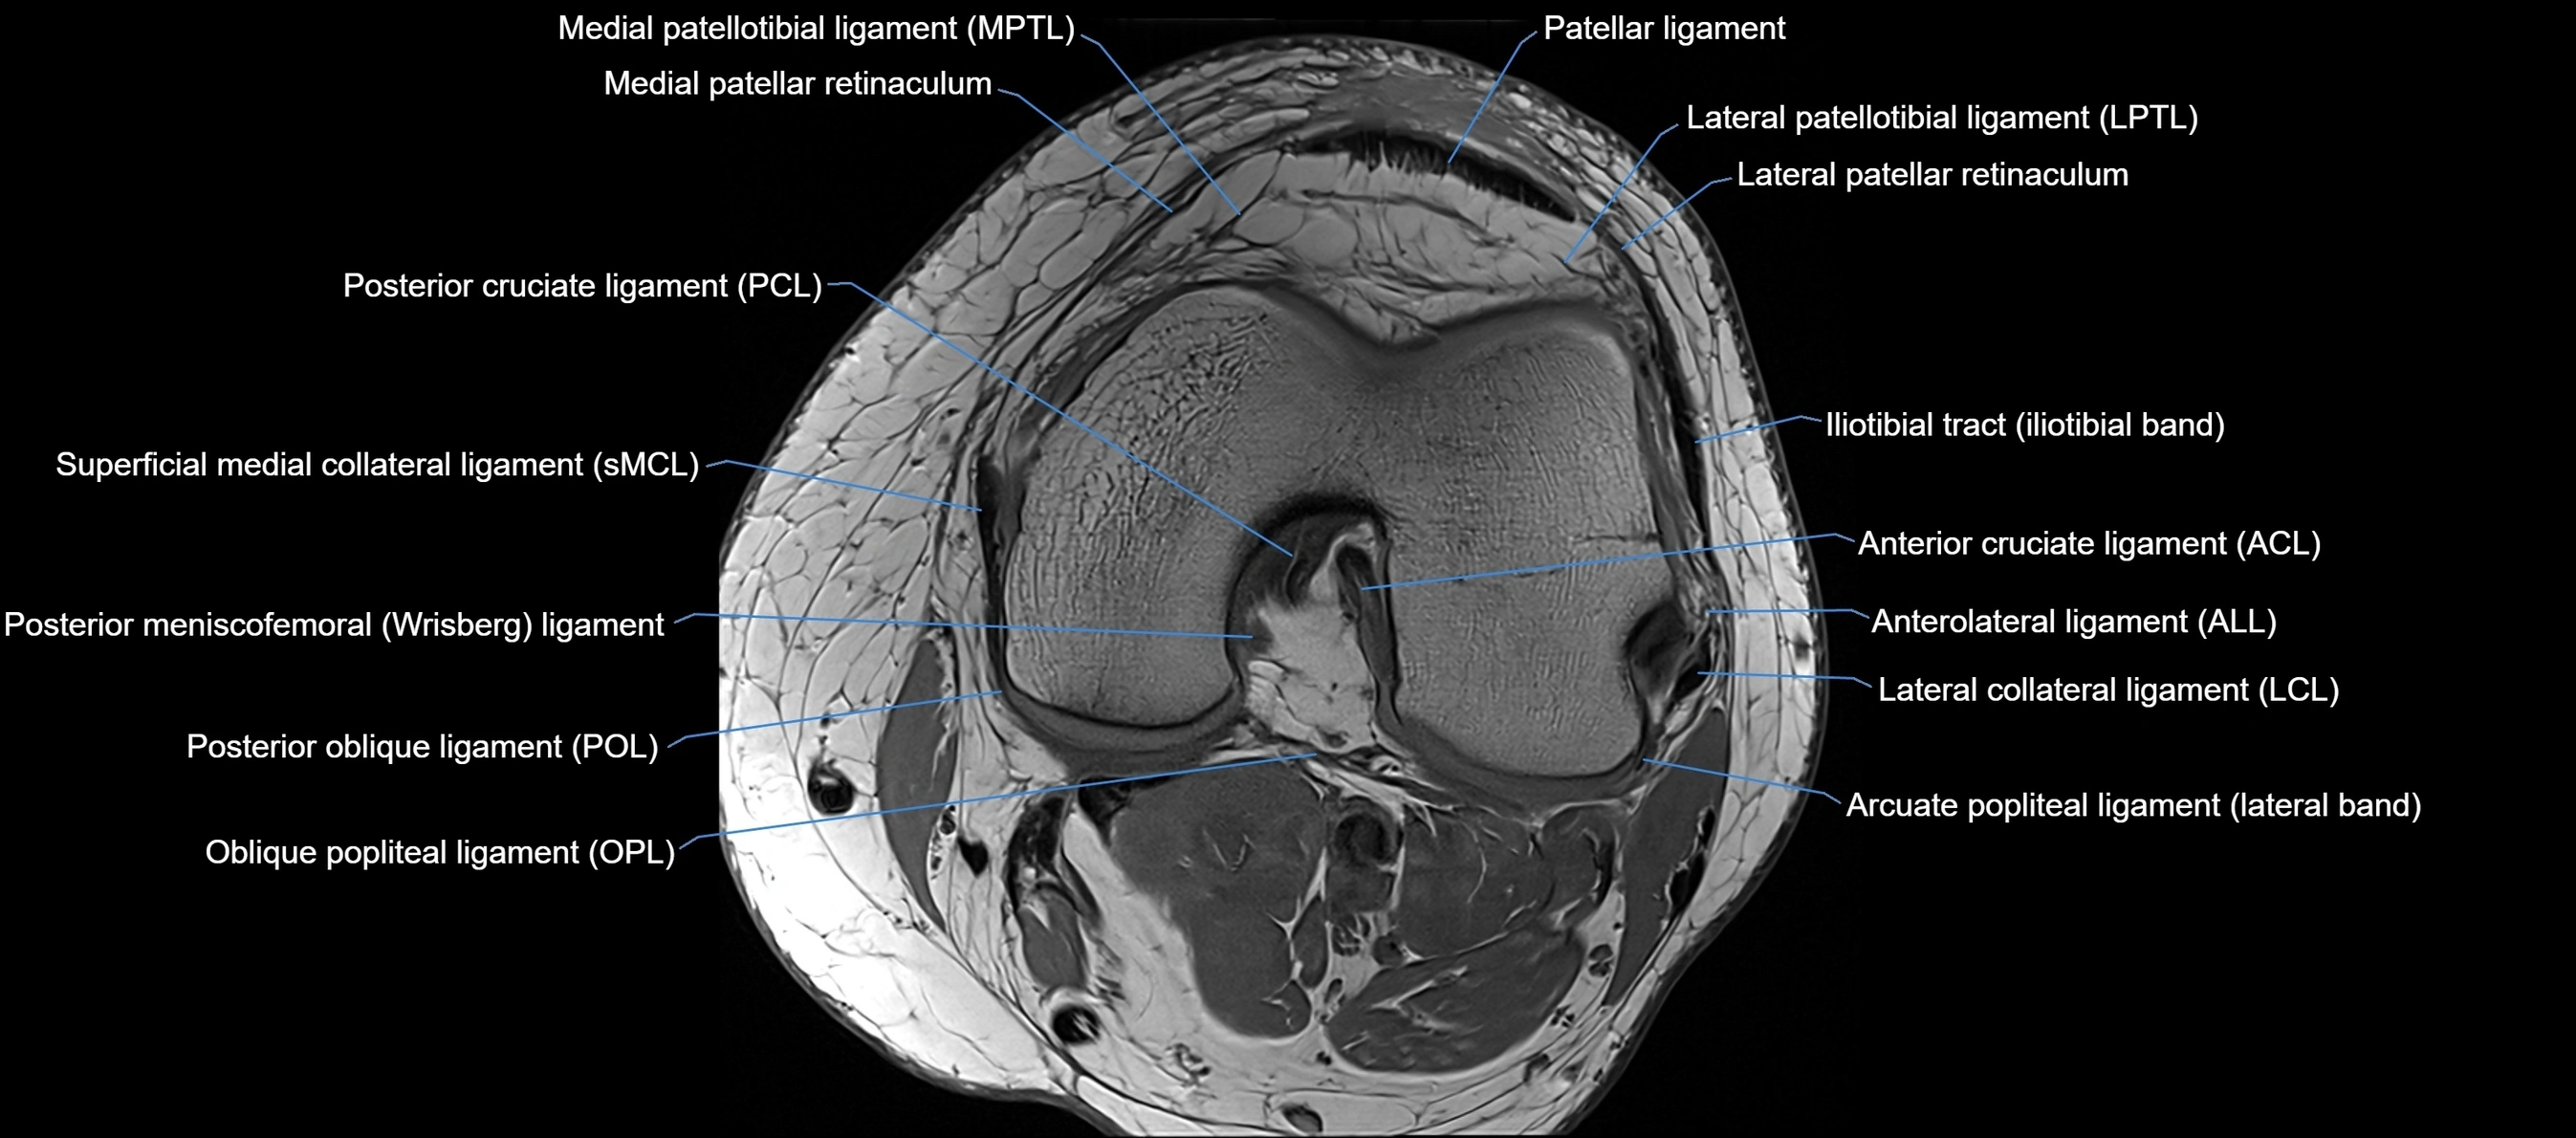

MRI images

image